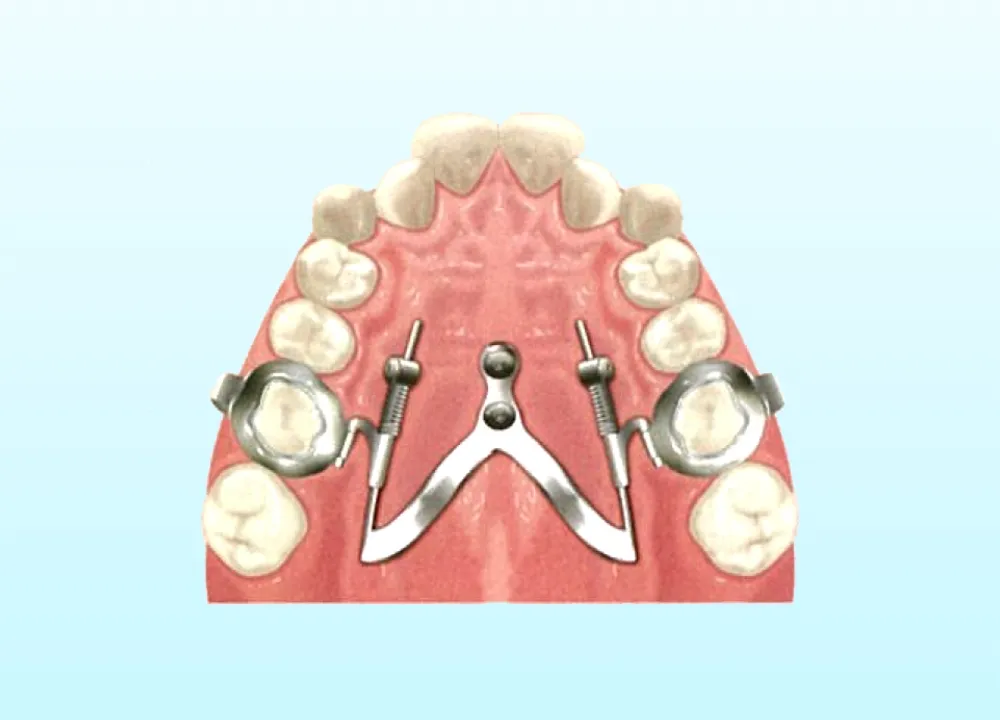

MSE(上顎骨骨格性拡大装置)は、矯正用アンカースクリューを使って上顎の骨を横に拡大する装置です。上顎の骨は左右に分かれており、その真ん中に正中口蓋縫合とよばれる骨のつなぎ目があります。MSEは、この骨のつなぎ目の右と左にそれぞれ2本ずつ、計4本のアンカースクリューを埋め込んで固定します。これによって左右の骨が少しずつ引き離され、その間に新しい骨が形成されることで、上顎の骨を横へと拡大できます。

具体的には、3Dスキャナーを使用して、アンカースクリューのヘッド部、上顎の天井の粘膜、歯の3次元的な位置関係をデータとして取得し、そのデータを基にCAD/CAM技術を駆使して矯正装置を設計・製作します。この3Dメタルプリント矯正装置は、歯への適合性と強度に優れており、幅広い症例に対応が可能です。

デジタル技術の進歩により、現在では3Dスキャナーで取得した患者様の口内の3Dデータを基に、CAD/CAM技術を活用して矯正装置の設計から作製まで行なうことが可能です。矯正用アンカースクリューと連結できる矯正装置も、3Dメタルプリント技術を用いて、患者様一人ひとりに合わせて精密に設計・製作することにより、対応可能な症例の幅が広がっています。